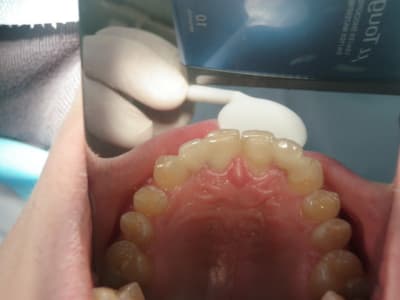

préparations pour bridge collé ...des commentaires?

Dsc00088 s3ie5k - Eugenol

Dsc00092 jmfmzu - Eugenol

tu fais un léger retour vestibulaire en mésial des canines, tu ne crains pas que ça devienne visible?

sinon occlusion? et ça parait bien.

pas vraiment de retour mais je souhaitais modifier légèrement l'aspect morpho des canines,

l'occlusion était un peu serrée au niveau des centrales ,mais il y a agénésie des 41 et 31 et j'ai remodelé le bridge collée antagoniste provisoire.

La 13 semble avoir une limite trop vestibulaire en effet...faudra voir le collage final...